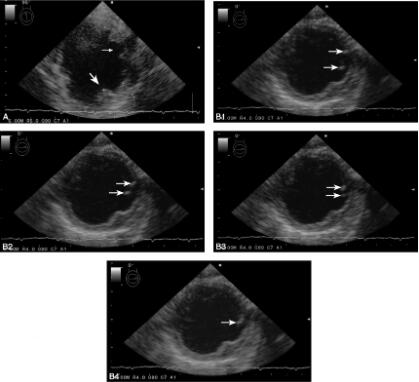

经食道超声(transesophageal echocardiography,TEE)检查(2009年5月29日):未见心内血栓及Moya征、静脉注射激活的生理盐水并做Valsalva负荷动作时右向左分流(+);升主动脉和主动脉弓见复杂斑块,斑块最大厚度10.3mm,可见溃疡,降主动脉见到活动性斑块,随心脏搏动而运动(图3)。

图3 TEE检查:A.主动脉弓见复杂斑块,最大厚度10.3mm(粗箭头),可见溃疡(细箭头);B1~B4.活动性斑块(箭头)随主动脉内的血流在一个心动周期内的运动幅度和活动轨迹

TEE检查没有发现心内血栓和Moya征(类似烟雾状的、容易形成心内血栓的血流情况),检查发现患者有卵圆孔未闭所致的少量右向左分流,如果患者同时存在静脉系统的血栓,有可能通过这种反常的分流引起多部位栓塞。除此之外,发现患者有严重的主动脉弓的粥样硬化性复杂斑块,斑块的最大厚度为10.3mm、伴有溃疡,在降主动脉见到活动性斑块。活动性斑块是重叠在斑块表面的血栓成分[6-8],其形成很可能类似急性冠脉综合征斑块破裂后血栓形成的过程,斑块破裂后启动凝血过程,表面形成新鲜血栓,有些血栓已经脱落,尚未脱落的部分还未机化,是新鲜、柔软的,会随着血流的运动而活动。有活动性斑块的患者栓塞事件的发生率明显高于无活动性斑块者[7]。主动脉的活动性斑块表明可能是短时间内刚发生了斑块破裂的事件,成为栓子来源,随着主动脉血流的涡漩和反流,血栓碎片脱落随机进入弓上各支脑供血动脉导致多灶性脑梗死,活动性斑块是多血管区域多发梗死的原因之一[9]。